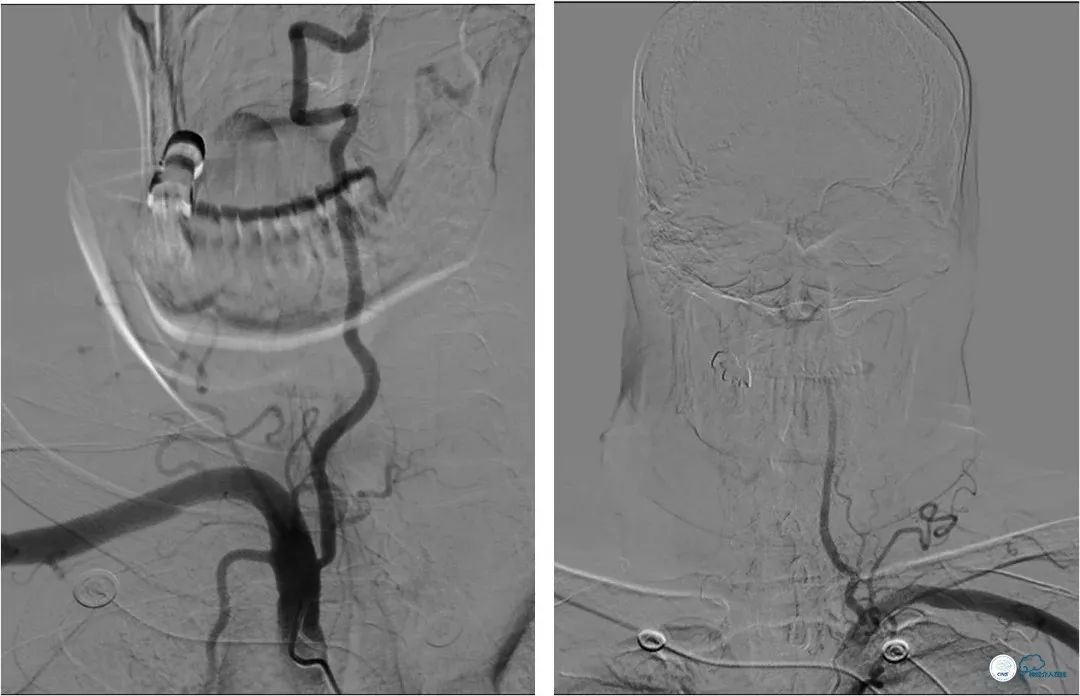

DSA提示:左椎动脉开口迂曲,右椎动脉开口中度狭窄(图5)。双椎动脉V4段与基底动脉交界处重度狭窄,左侧狭窄程度更重(图6,7)。

图5

图6

图7